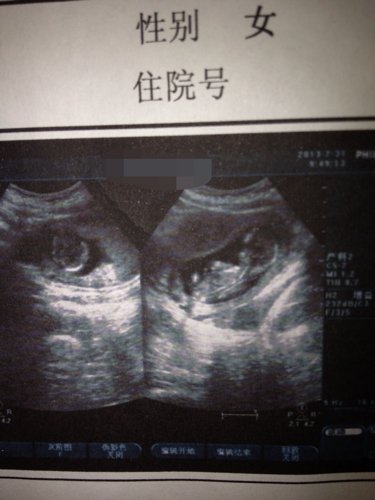

准妈妈一枚,好奇肚里的宝宝是帅哥还是美女?有谁会看B超?来帮帮忙 点击展开 匿名用户 2013-08-13 00:17 为您推荐: 其他回答 应该是个男的! 匿名用户 2013-08-13 17:42 看体型是男的!好像还能隐约看到弟弟!恭喜了! 匿名用户 2013-08-13 00:20 相关问题 好奇:为什么个人感觉世上的帅哥比美女多? 怎样使自己更成熟?更让女孩有好奇感,让人猜不透? 我的宝贝留级了 求发动 好期待是美女还是帅哥